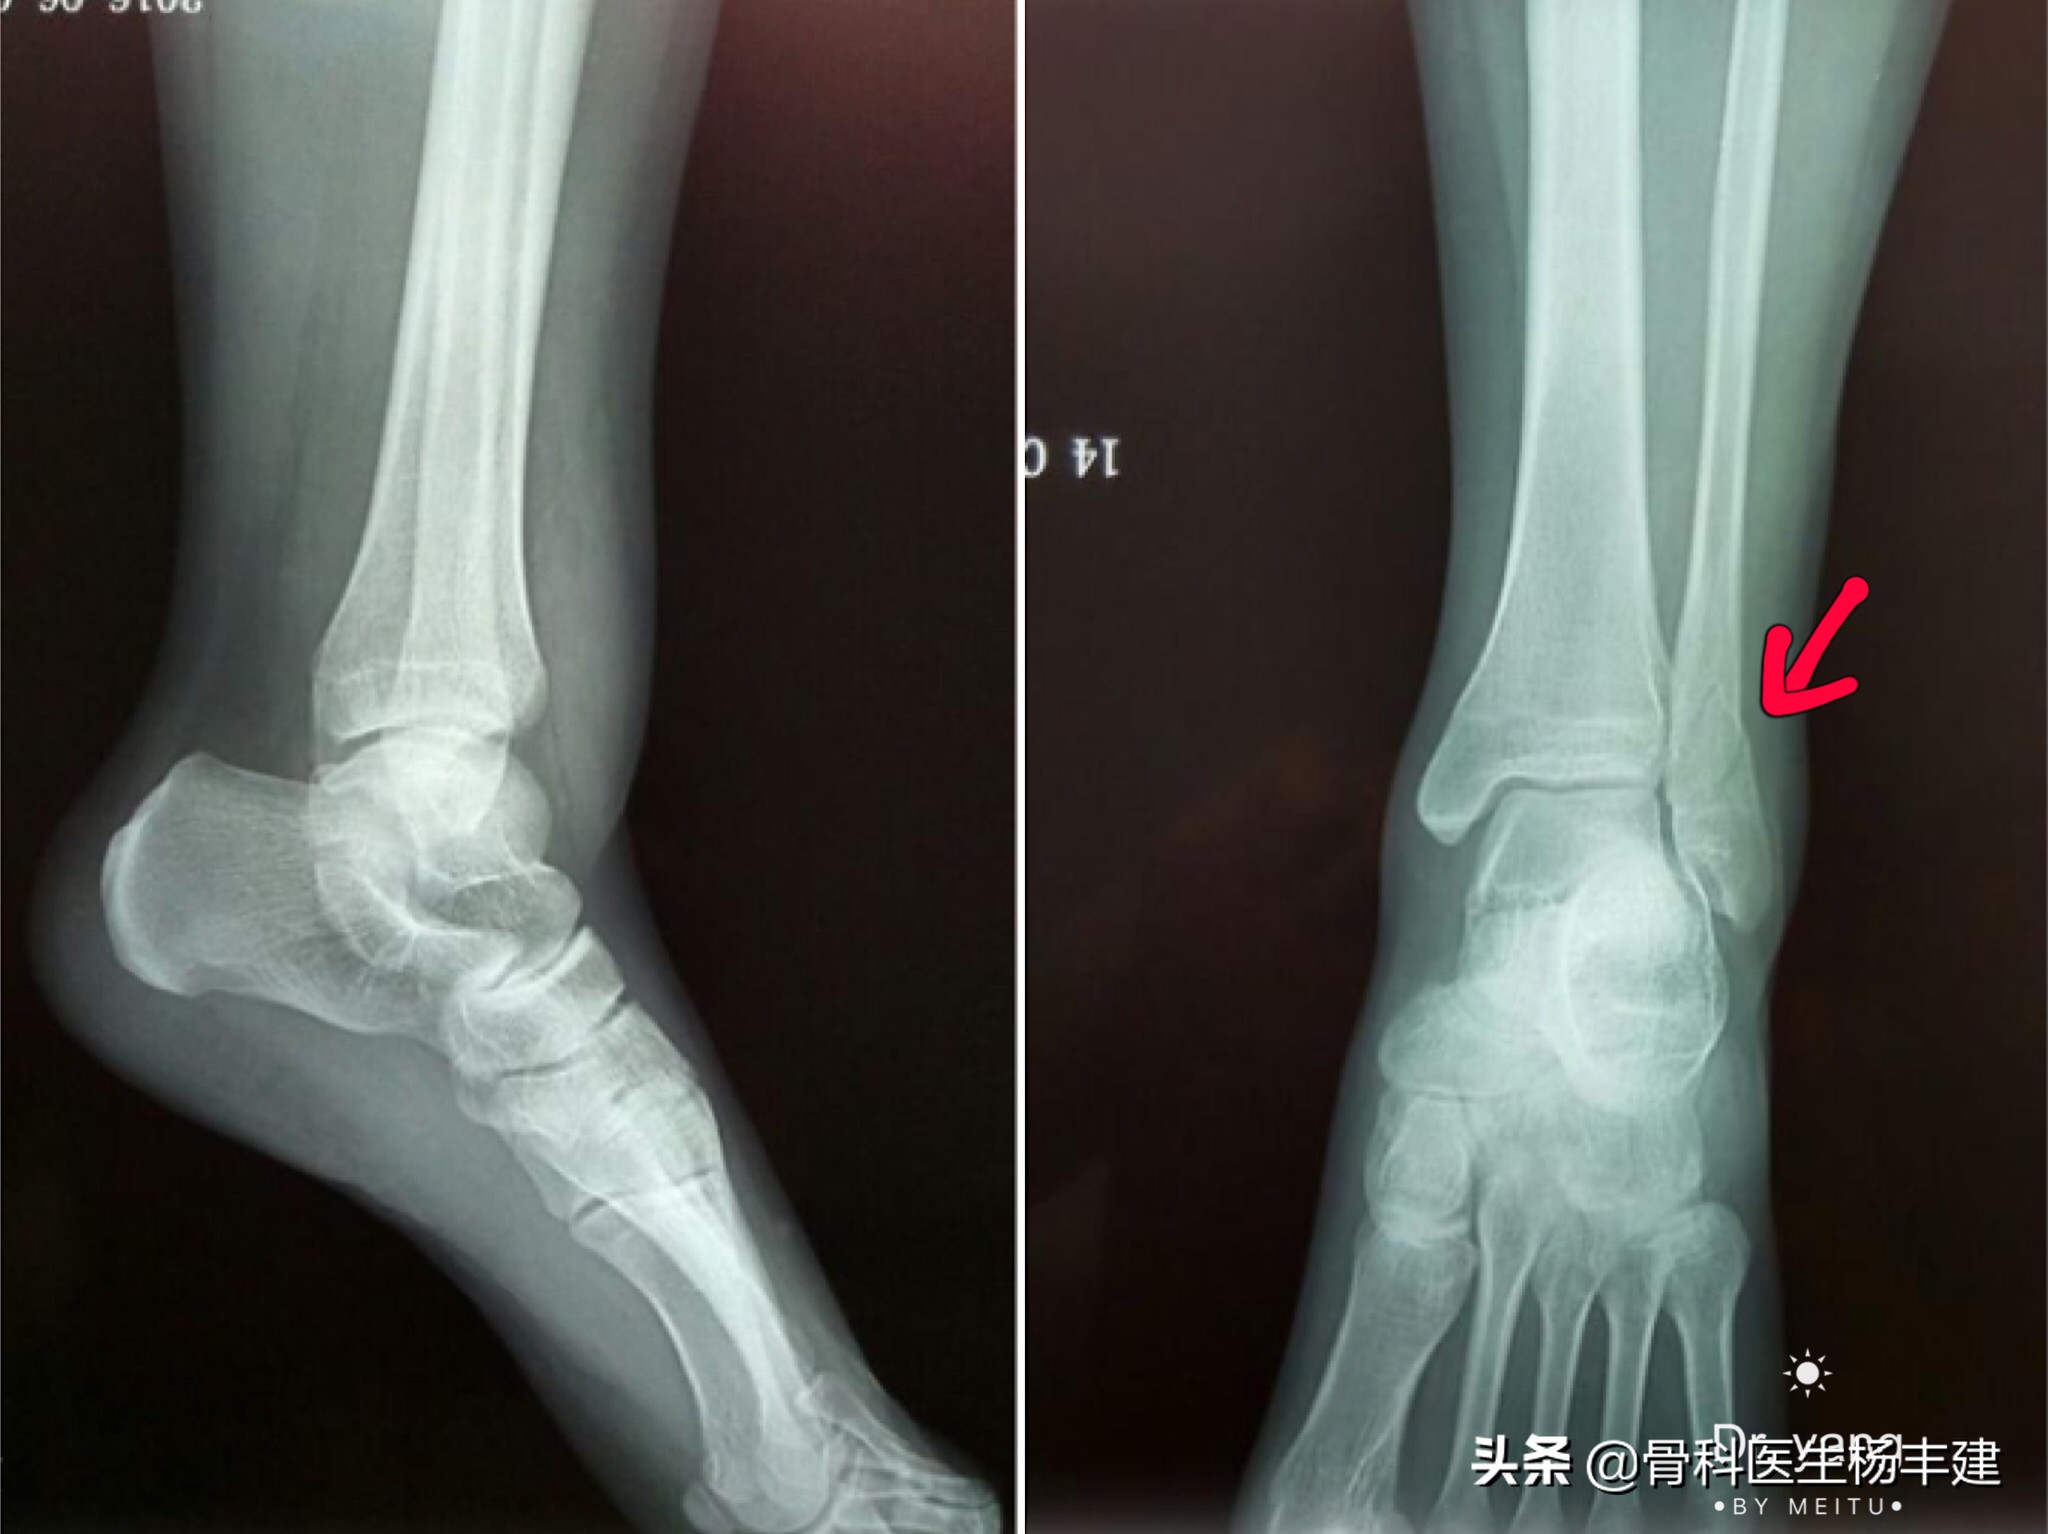

前面我们提到过,踝关节一旦出现骨折,往往会造成外踝或者内踝,甚至连同后踝的骨折。如果外力相对比较小,也可能会出现单处骨折,比如说单纯外踝的骨折。如果说至于单处骨折,并且骨折没有移位,踝穴两侧的关节间隙均匀,是可以采取保守治疗的,尤其是年纪稍微大一些的病人。(由于X光片的重叠效应,后踝骨折容易漏诊,关节周围骨折最好有CT检查)

红色箭头处显示外踝骨折,但几乎没有移位,踝穴两侧的关节间隙均匀,没有增宽的表现

3,那么什么样的骨折需要做手术呢?如果损伤造成了两处,甚至两处以上的骨折(比如说内踝、外踝同时骨折,甚至连同后踝一起骨折),踝关节的稳定性往往会遭到破坏,从而出现比较明显的移位,这种情况是需要做手术治疗的。

内外踝均有骨折,并有明显移位,是手术治疗的指征